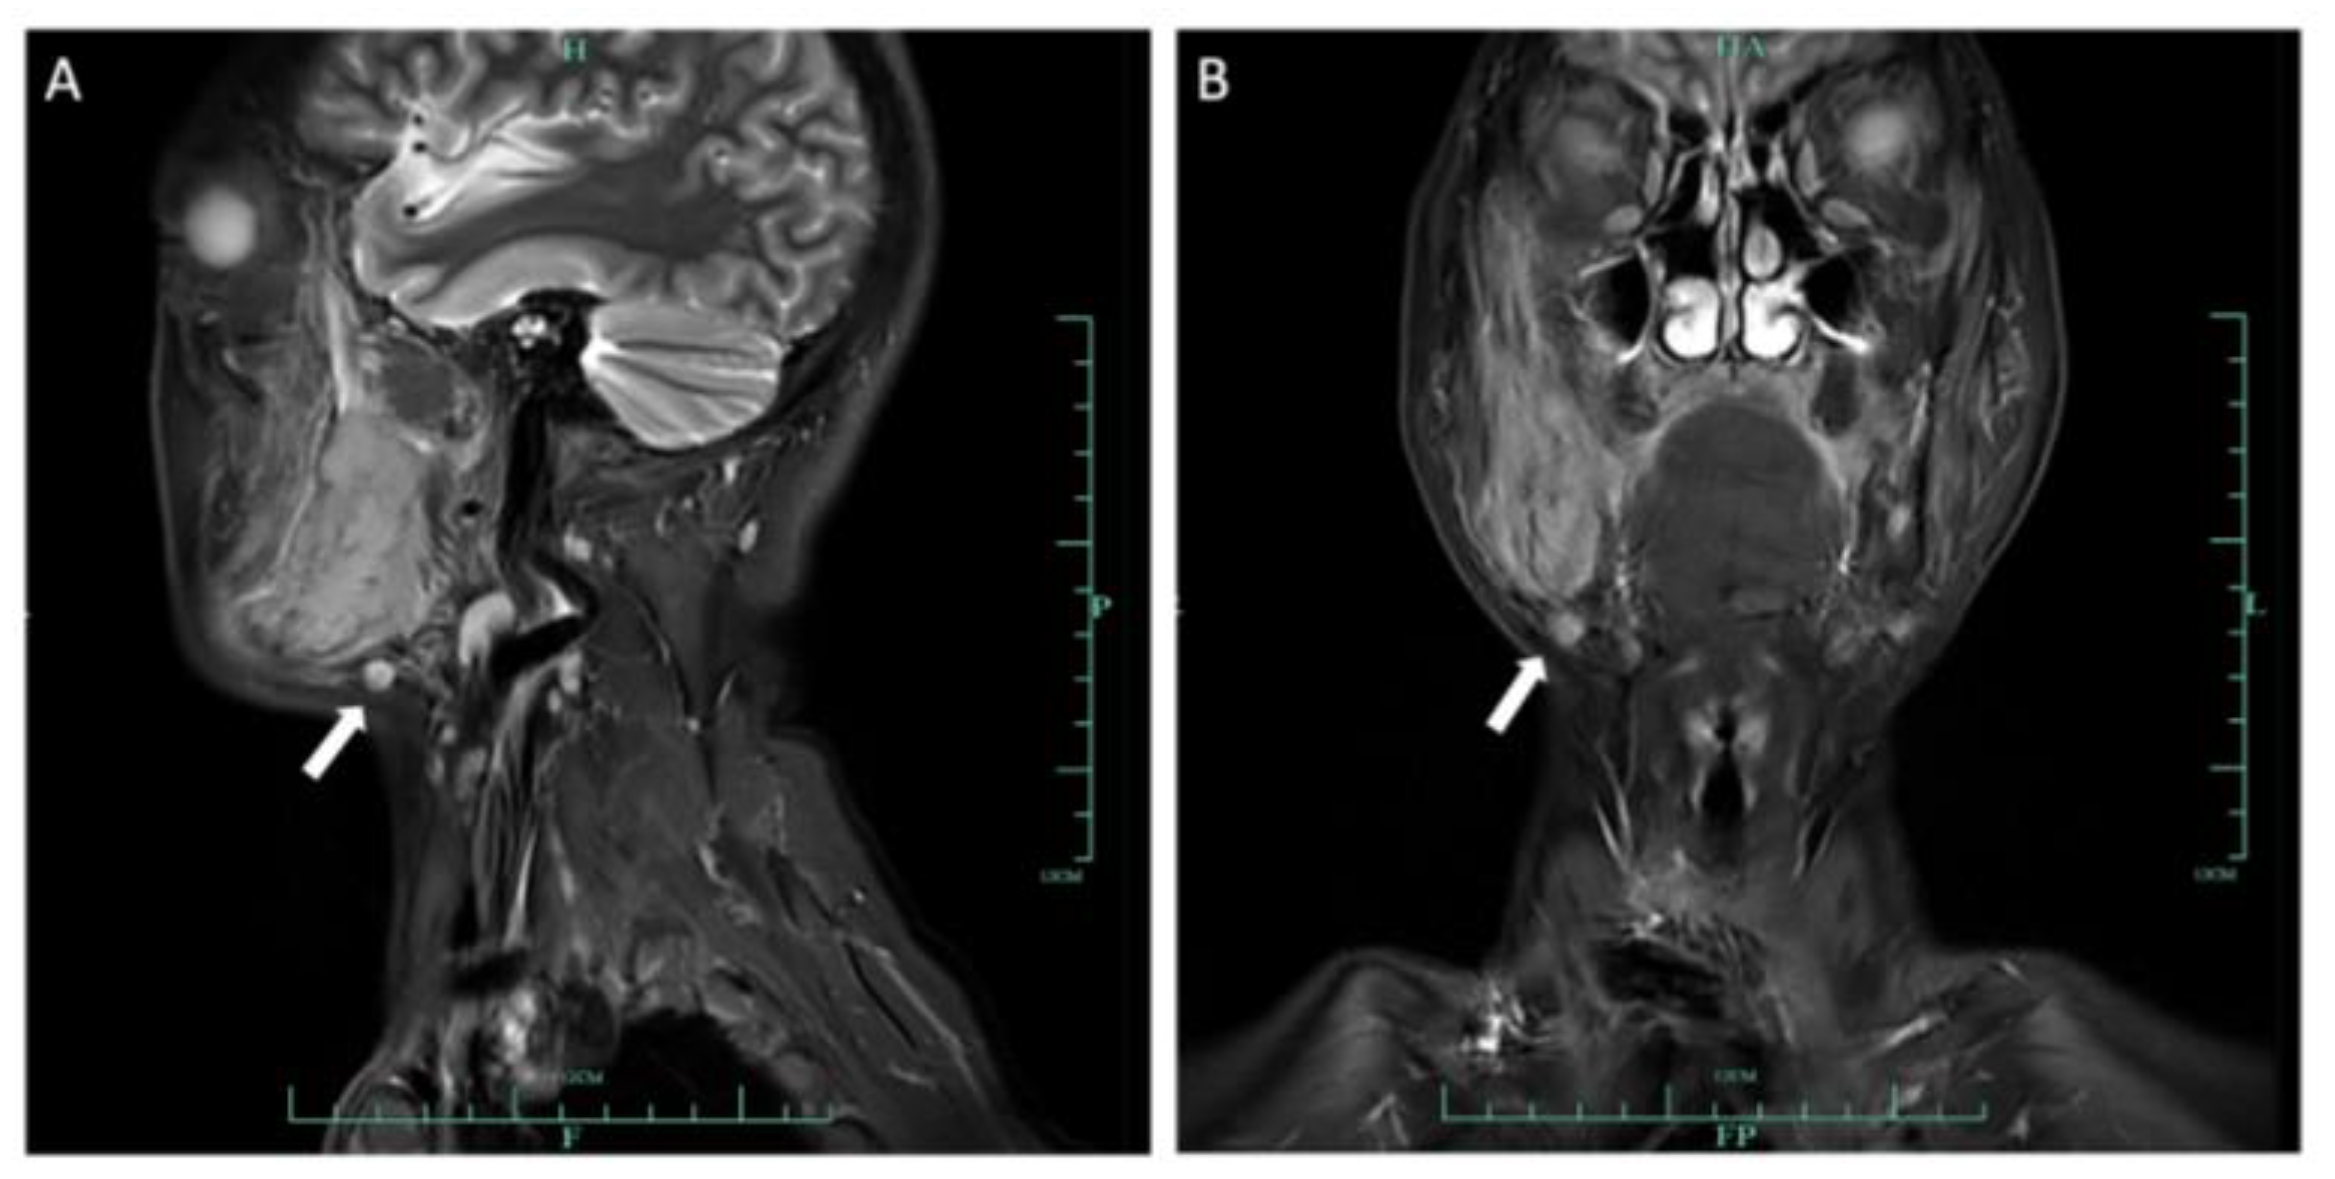

2.1. Case 1

2.2. Case 2